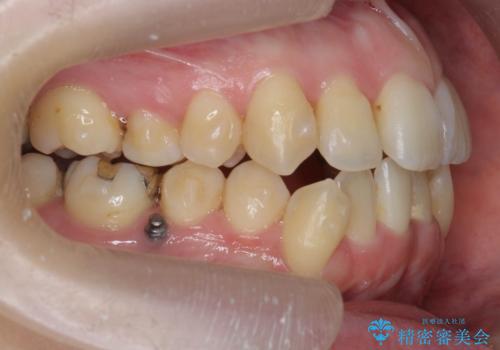

前歯のがたつき すれ違い咬合のマウスピース矯正治療

- 前歯のがたつきや歯の角度、矯正治療を希望され来院されました。

下顎が前にある咬合関係を可及的に咬合移動で改善し、IPR、下顎3前歯の仕上げで行うマウスピース矯正を計画します。